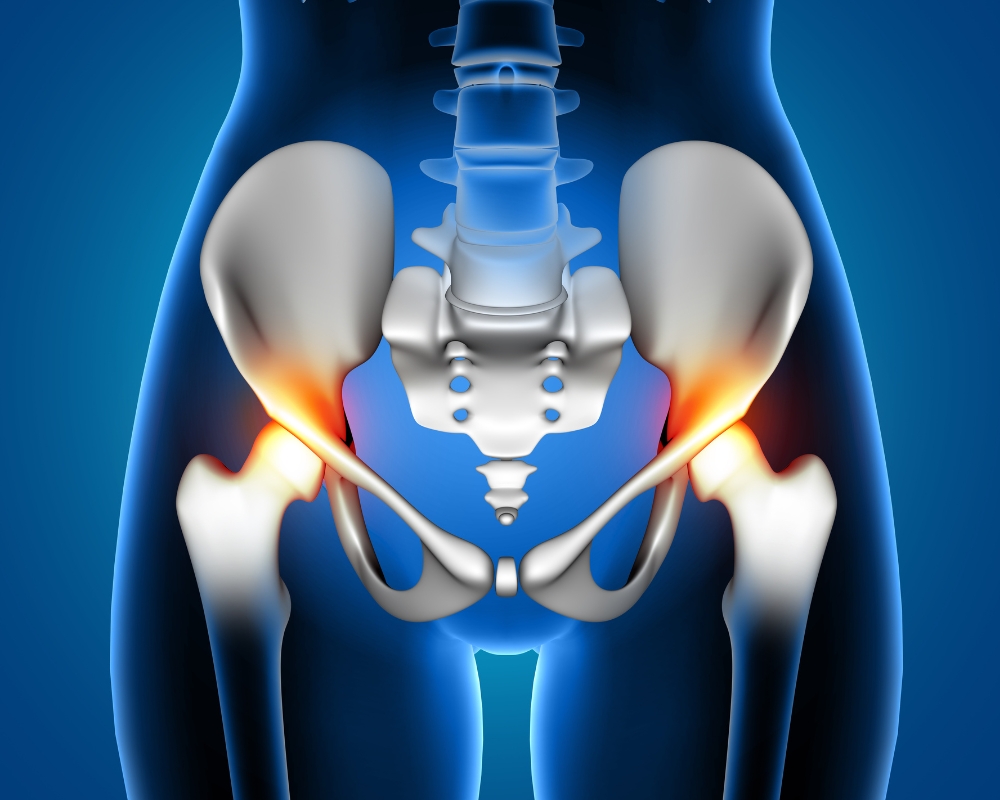

Khớp háng được cấu tạo từ chỏm xương đùi hình cầu và ổ cối xương chậu hình lõm. Hai bộ phận này đều có lớp sụn bao bọc giúp bảo vệ đầu xương và giảm ma sát khi vận động.

Thoái hóa khớp háng là tình trạng sụn ở hai đầu khớp háng bị mài mòn theo thời gian, khiến cho hai đầu xương cọ xát vào nhau gây đau, đặc biệt là khi vận động. Bệnh ảnh hưởng nghiêm trọng đến cuộc sống sinh hoạt và khả năng vận động bình thường của người bệnh. Bên cạnh việc gây đau, thoái hóa khớp háng còn khiến cho các thành phần gồm sụn khớp, xương dưới sụn, dây chằng, cơ, màng hoạt dịch… bị tổn thương theo.